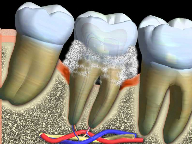

Recurrent decay (decay around existing fillings) can be detected during recall exams. If left untreated, the decay will spread underneath the filling and the tooth may require extensive treatment.